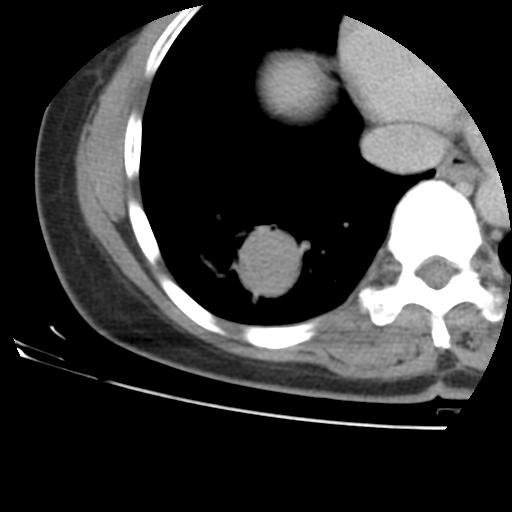

右肺下叶类癌

女 46岁,咳嗽咳血10月

【linyiming】右肺下叶见类圆形软组织影,边缘欠规整,略分叶状。考虑炎症假瘤可能?

未排除周围型肺癌。建议CT增强。

【aosangwa】肺癌的主要特征是:毛刺征、分叶征及胸膜凹陷征,此病例位于右肺下叶距胸膜很近,但没有胸膜凹陷征,其周围像示渗出性病变,病灶在两窗上没有大小没有发生大小改变。

考虑其良性肿瘤,炎性假瘤可能性大,其主要鉴别是:结核球、周围型肺癌、血管瘤

病理诊断类癌(周围型)。